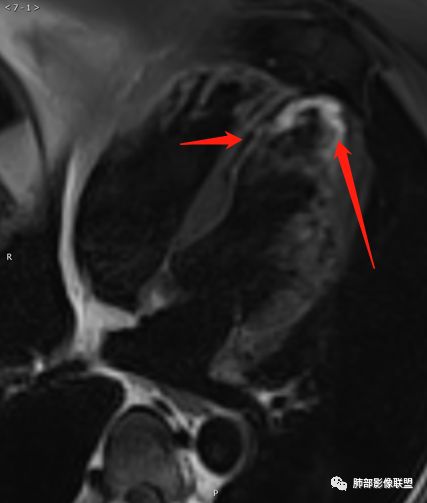

病例三

● 男,20

● 无高血压病史

病例解析

征象:

左心室心肌不对称性肥厚,间隔壁为著

舒张功能减低

收缩期二尖瓣前叶前移,静息状态下左心室流出道梗阻

收缩期见二尖瓣区向心房侧束状低信号

心包内见液性信号

LGE:左心室心肌中层条片状高信号

诊断:

非对称性梗阻性肥厚型心肌病

间隔壁最厚室壁厚度>30mm

左心室心肌中层弥漫心肌纤维化

左房增大,二尖瓣关闭不全

心包积液